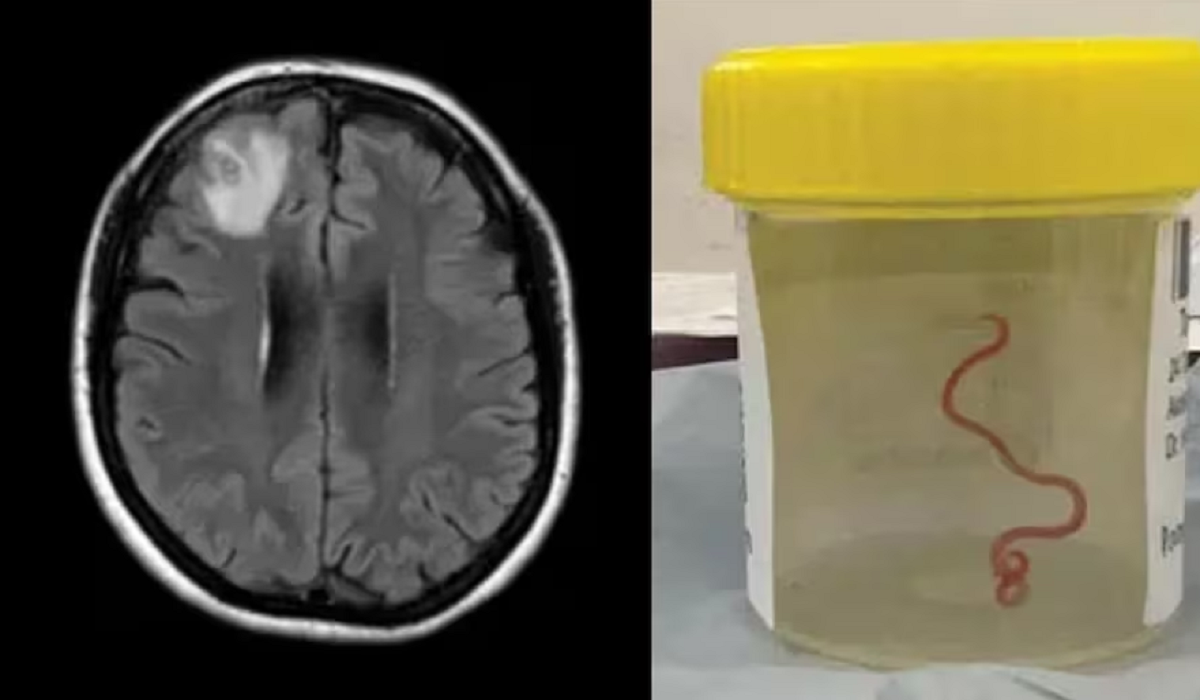

महिला में पिछले साल डिप्रेशन और भूलने की बीमारी के लक्षण भी दिखने लगे। उसे कैनबरा अस्पताल रैफर किया गया। हाल ही उसके दिमाग के एमआरआइ स्कैन के बाद सर्जरी का फैसला किया गया। डॉक्टर सर्जरी के दौरान उसके दिमाग के अंदर जिंदा कीड़ा देखकर हैरान रह गए। महिला की हालत फिलहाल स्थिर बताई जाती है।

कैनबरा अस्पताल के संक्रामक रोग चिकित्सक डॉ. संजय सेननायक ने कहा, कोई आसानी से यकीन नहीं करेगा कि महिला के दिमाग में एक जिंदा कीड़ा रेंग रहा था। न्यूरोसर्जन डॉ. हरि प्रिया बांदी के मुताबिक यह तीन इंच लंबा, चमकीले लाल रंग का कीड़ा था। प्रयोगशाला में जांच के बाद वैज्ञानिकों ने बताया कि यह पैरासाइट राउंडवॉर्म था। महिला एक झील के पास रहती है, जहां कार्पेट अजगर ज्यादा पाए जाते हैं।